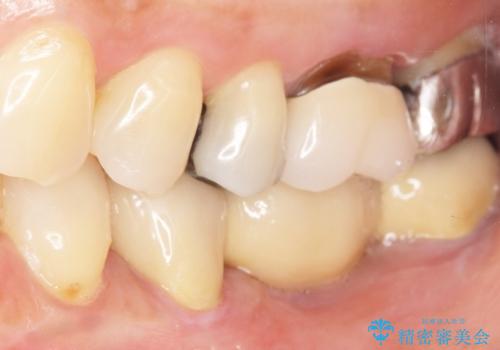

精査したところ、ブリッジの支台歯となっている左下の奥歯(左下7)は大きなう蝕により神経が死んでいました。

根管治療後、メタルボンドブリッジによる補綴治療を行いました。

- ¥462,000 (根管治療×1本、土台×1本、仮歯×3本、クラウン×3本) ※税込費用は治療当時の料金となります